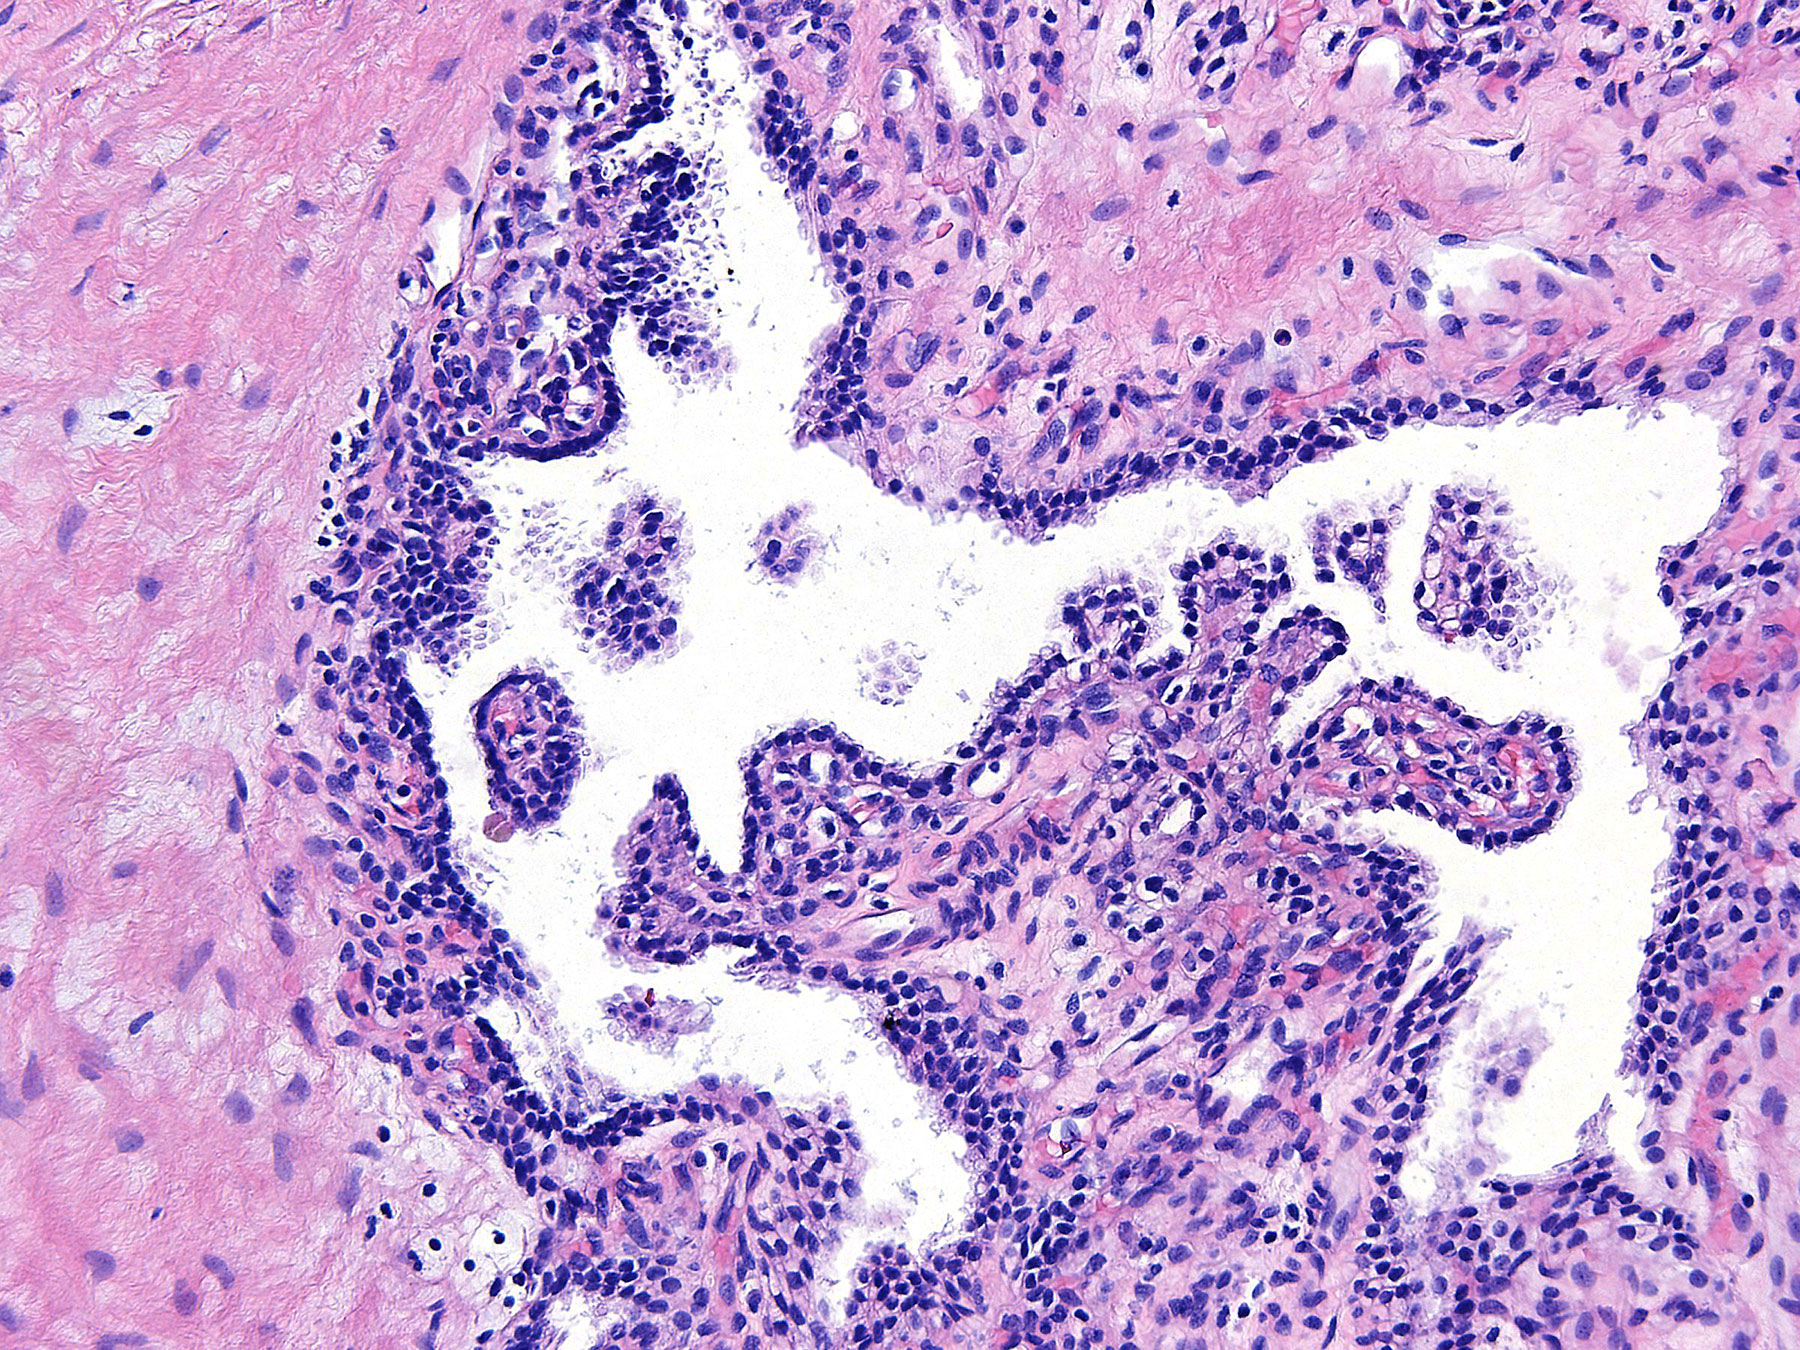

Figure C. H&E x20

Histology: The sections show several cystic structures lined by single layers of flattened and cuboidal cells separated by fibrous septa.